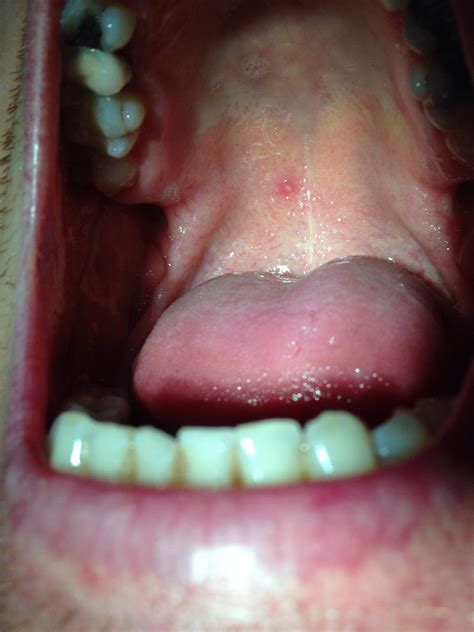

The symptoms of a mucocele roof of mouth can vary, but they generally include:

• A small, painless bump on the roof of the mouth

• Swelling and discomfort

• Difficulty eating or drinking

• Interference with speech

In some cases, the mucocele may rupture, releasing the mucus and causing temporary relief. However, the lesion often recurs if the underlying cause is not addressed.